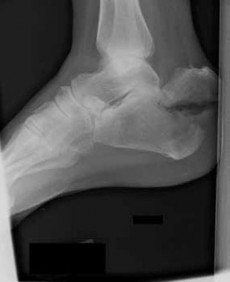

A 23-year-old carpenter fell off a roof 4 weeks ago. He has pain in the ankle and a deformity. The lateral radiograph is presented (Slide). Which of the following treatments is most likely to return this patient to work with a functioning foot and ankle: